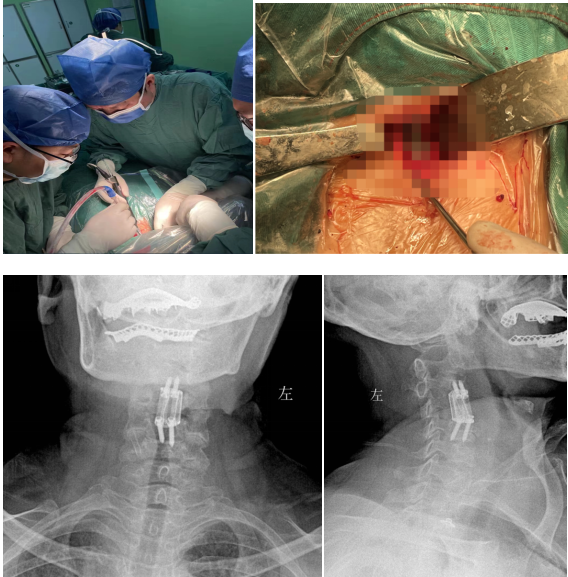

經(jīng)過多學科會診(MDT),完善術(shù)前相關(guān)準備后,由蘇光輝主任主刀,帶領(lǐng)團隊錢軍、鄧三東等,精準完成病灶清除、椎管減壓、植入3D打印cage等流程,在麻醉師、手術(shù)室的全力配合下,整臺手術(shù)一氣呵成,手術(shù)順利。

術(shù)后影像學顯示,植入內(nèi)植物位置滿意,與終板匹配性良好,穩(wěn)定性佳。術(shù)后患者生命體征平穩(wěn),癥狀明顯緩解,活動良好,目前已出院。